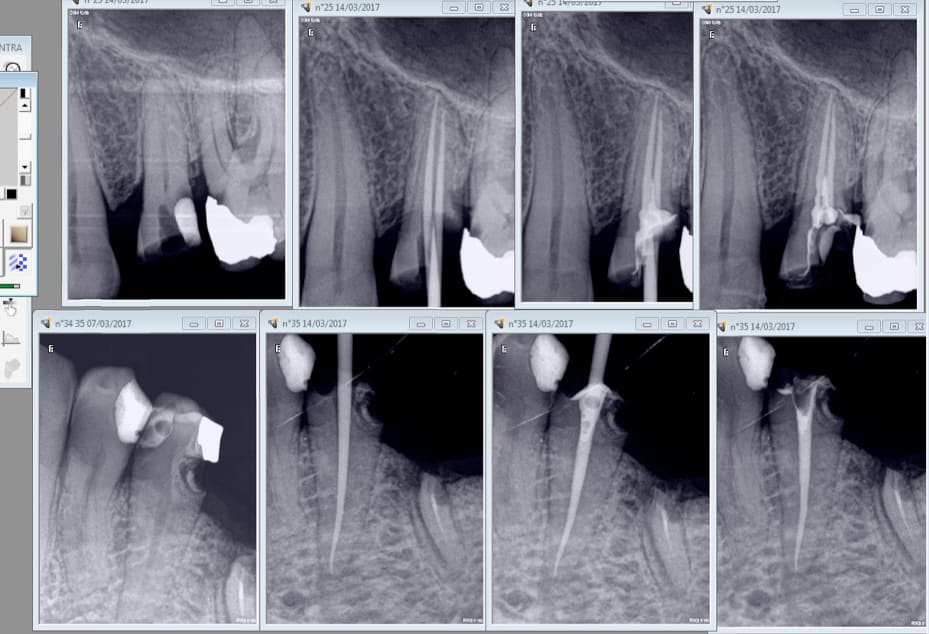

Mes endos masters commencent à merder donc j'ai utilisé le joypex 5 acheté 80 euros sur Ebay.

Résultat : 20 mn l'endo sur cette 26.

Ces 2 là 1h de RDV expédiées en 25 mn. -) Malheureusement j'avais un doublon de RDV. Sinon ca aurait été passé au taille crayon dans la foulée. -)

J' alterne le localisateur sur l'entran ( S1) et WDW connect ( réciproc R25 blue)